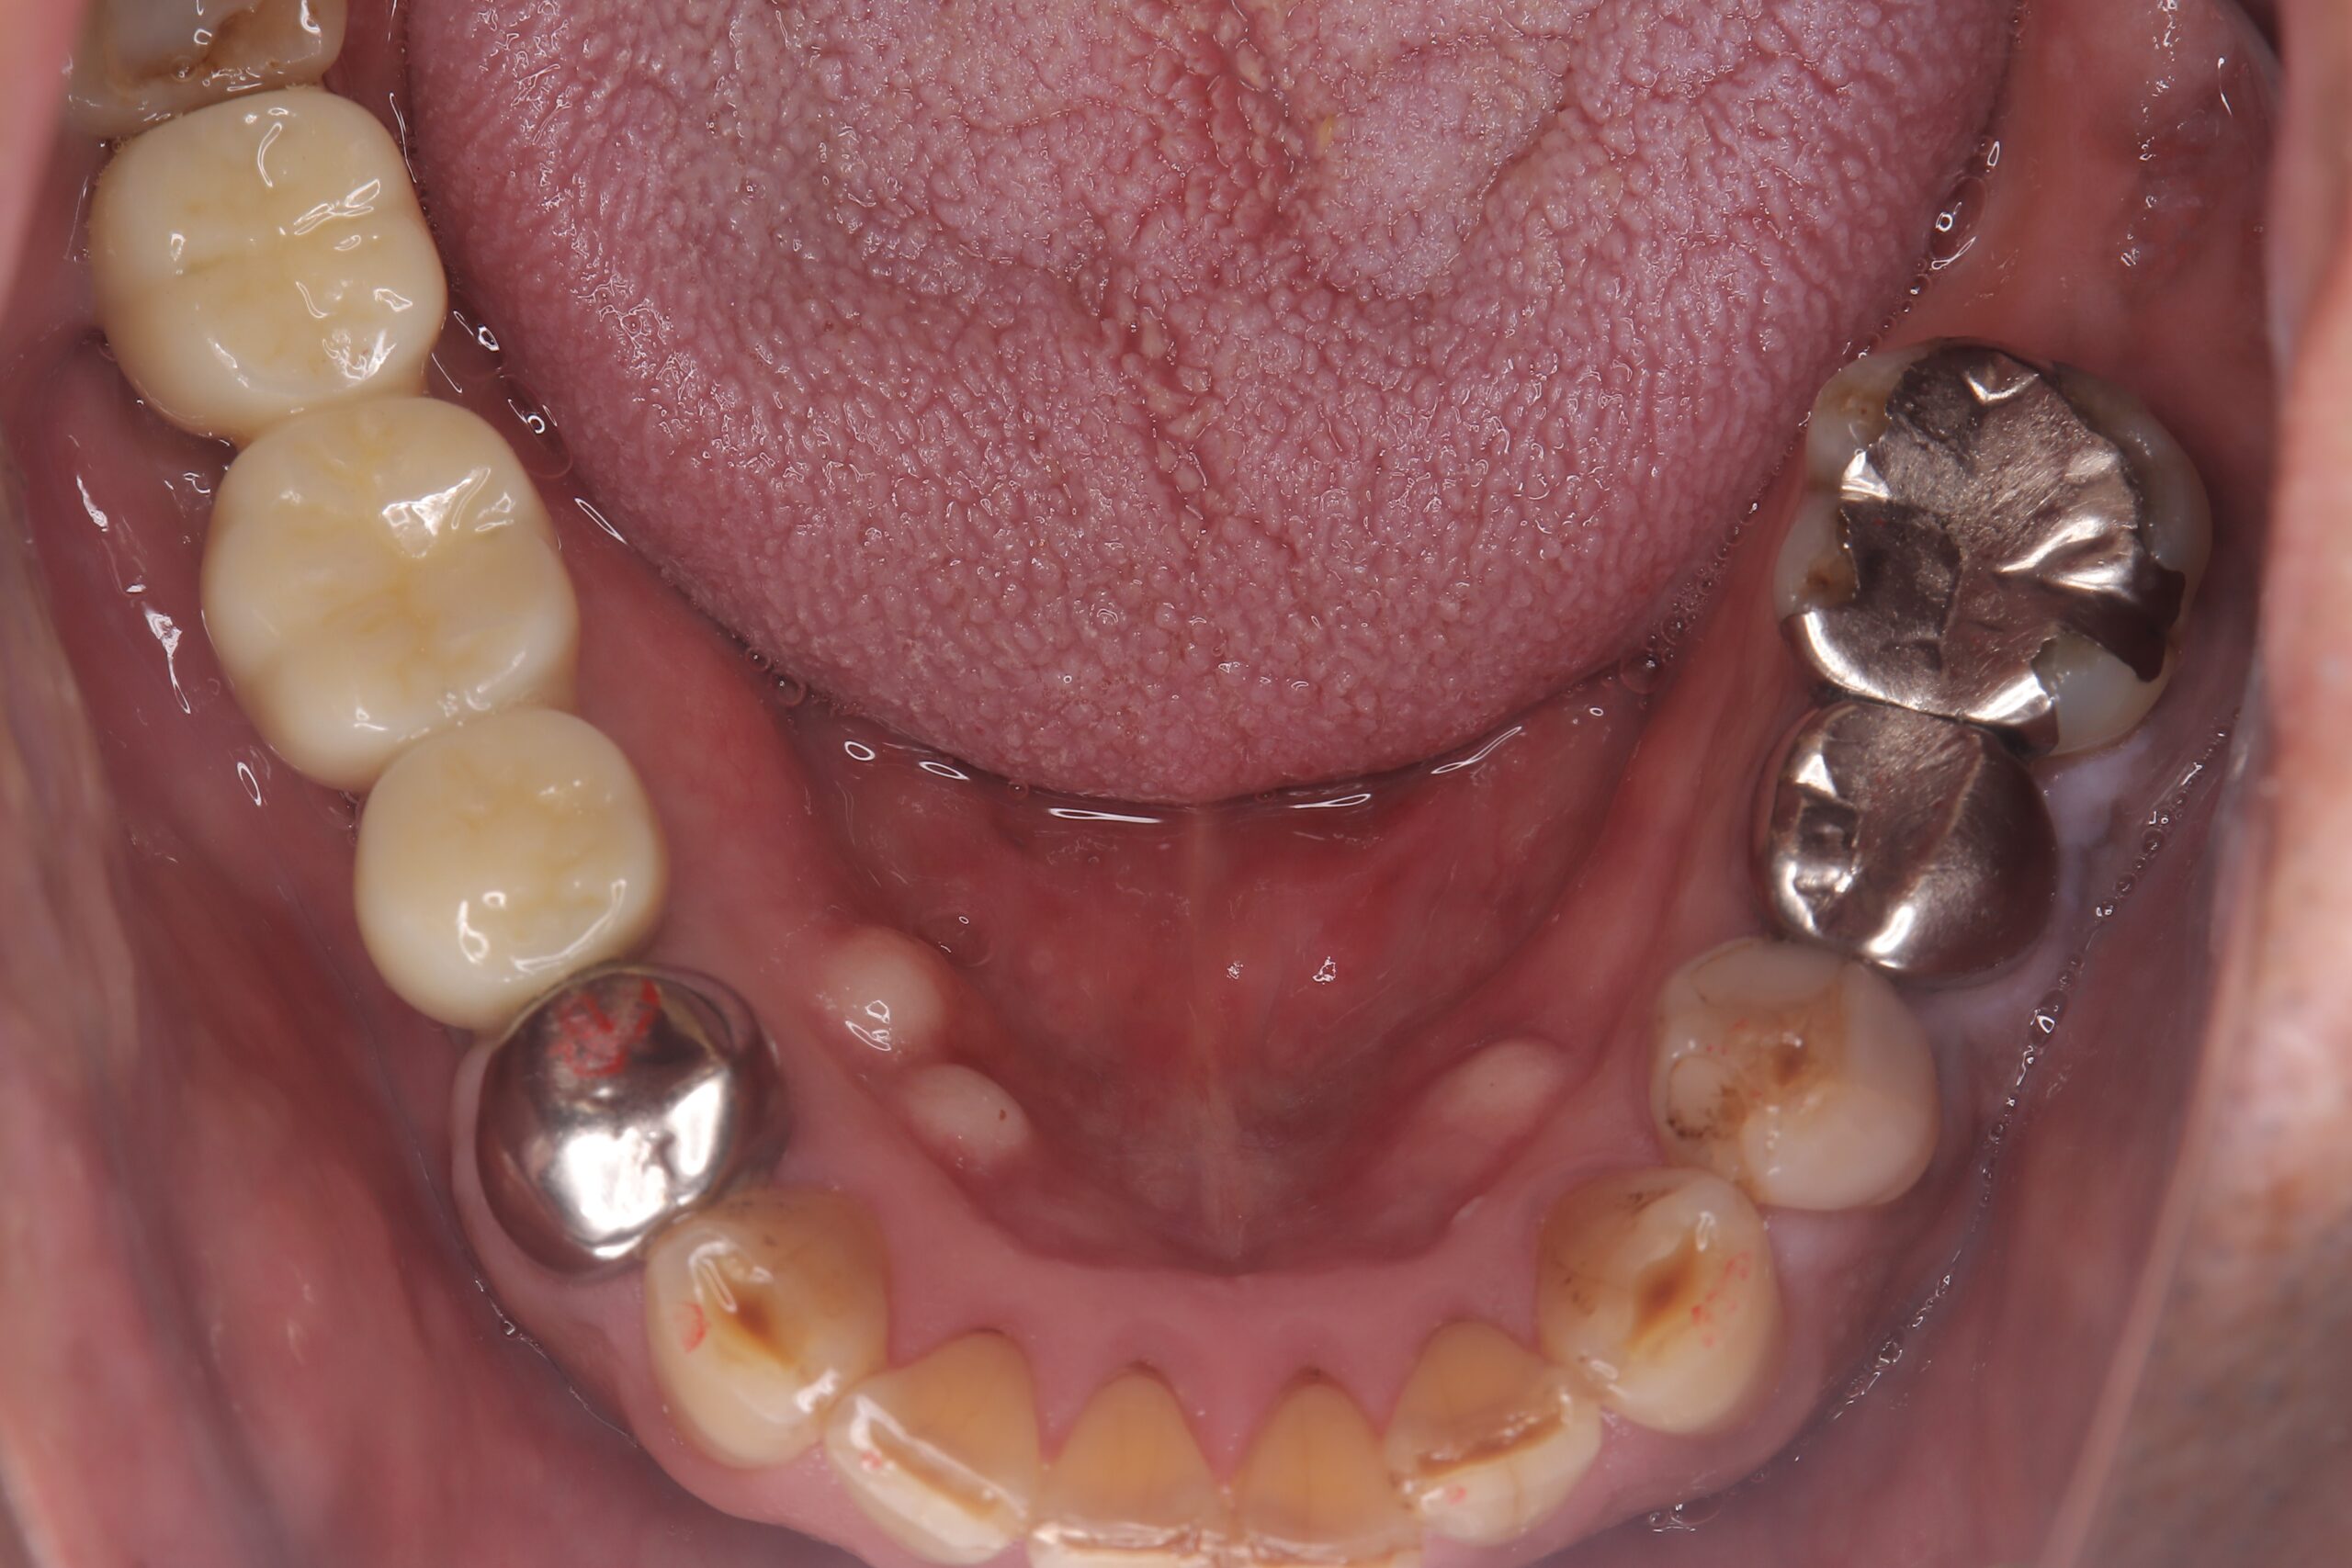

治療後

インプラントを入れることで反対側の歯を守る効果もございます。

当院ではジルコニアセラミックの冠を使用します。